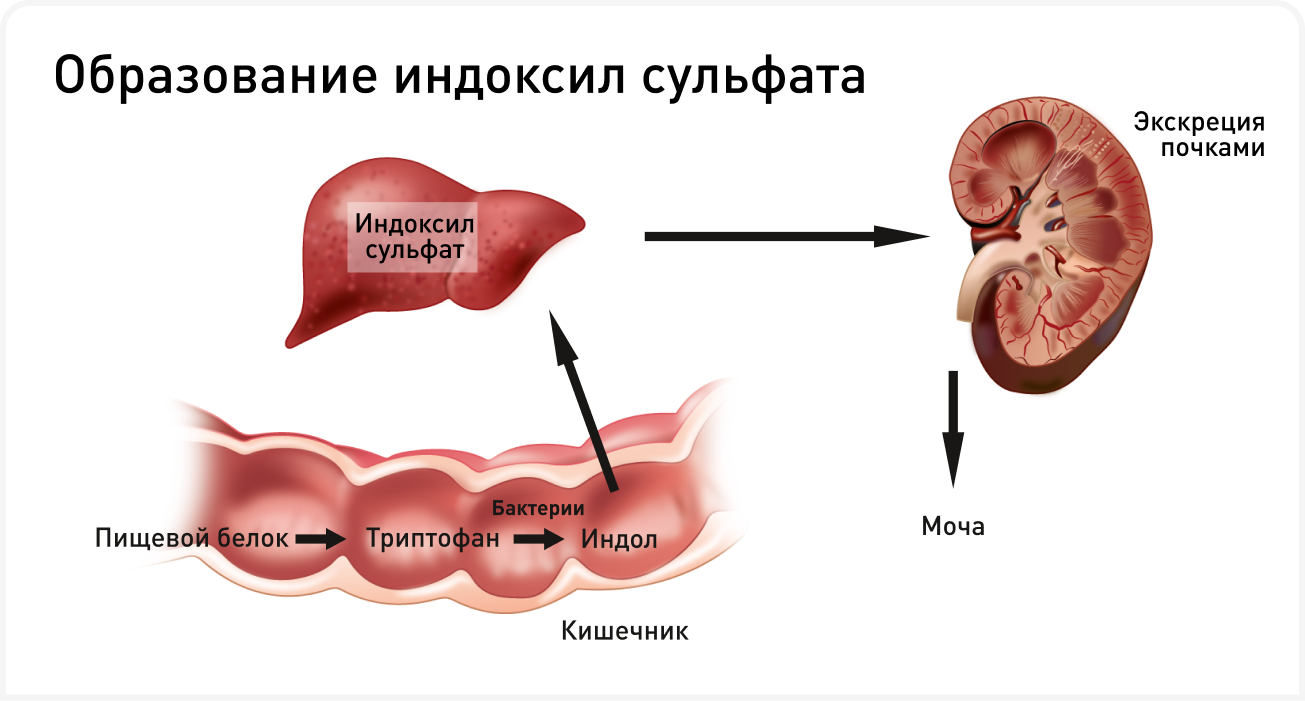

Индол и п-крезол, предшественники уремических токсинов, образуются при катаболизме белков микробиотой толстой кишки (4, 5). Индолы образуются в результате метаболизма триптофана пищи под действием триптофаназы кишечной микробиоты, например, микроорганизмов Escherichia coli (E. coli), Proteus vulgaris и Bacteroides spp. (Рисунок 2). П-крезол образуется в результате частичного расщепления тирозина и фенилаланина многими облигатными или факультативными анаэробами кишечника, включая микроорганизмы родов Bacteroides, Lactobacillus, Enterobacter, Bifidobacterium и Clostridium. Индол и п-крезол всасываются, а затем сульфируются в печени с образованием связанных с белками уремических токсинов IS и pCS соответственно. Эти токсины обычно выводятся почками, поэтому у пациентов с болезнью почек накапливаются в системном кровотоке. Выработке уремических токсинов, происходящих из толстого кишечника, дополнительно способствует дисбиоз, инициируя порочный круг (4, 5). Нарушение усвоения белка в тонком кишечнике при ХБП увеличивает содержание белкового субстрата в просвете кишечника, что способствует размножению протеолитических бактерий, продуцирующих предшественники уремического токсина. Определенную роль также может играть запор, сопровождающийся длительной задержкой каловых масс в толстой кишке; у пациентов с ХБП, страдающих запорами, уровень уремических токсинов выше, чем при нормальной балльной оценке фекалий (6).